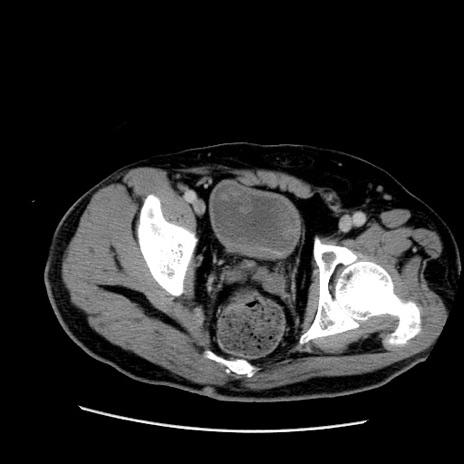

症例22(横断像)

【症例】50歳代男性

【主訴】腹痛

【現病歴】AVMからの被殻出血のため回復期リハ病棟入院中。 本日午後3時頃急に下腹部痛が出現した。

【既往歴】AVM、被殻出血、虫垂炎、高血圧

【身体所見】意識晴明、左半身不全麻痺、会話の理解は良好、36.5°C、腹部:膨隆、全体に板状硬、下腹部正中に圧痛点あり、反跳痛-、筋性防御不明、右下腹部にope scar

【データ】WBC 9400、CRP 0.06